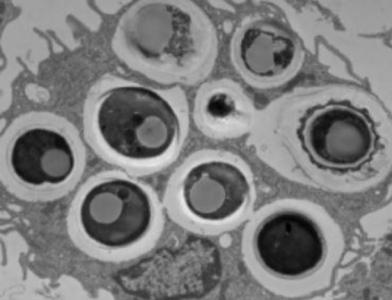

Quels mécanismes ? L’étude de souris modèles de cicatrisation intestinale altérée représentatives des lésions intestinales observées chez les patients atteints de la maladie de Crohn, constate que les niveaux de D. hansenii sont également significativement plus élevés dans les plaies non cicatrisées. La levure se développait dans ces plaies plutôt à proximité des macrophages.

D. hansenii n'est pas globalement pro-inflammatoire : la levure contribue plutôt à la MICI en augmentant les niveaux d'une cytokine spécifique appelée CCL5 (chimiokine ligand 5). Les chimiokines telles que CCL5 sont nécessaires pour recruter d'autres cellules inflammatoires. Cibler CCL5 ou la levure elle-même pourrait constituer une approche thérapeutique efficace chez les patients atteints de la maladie de Crohn, infectés par D. hansenii.